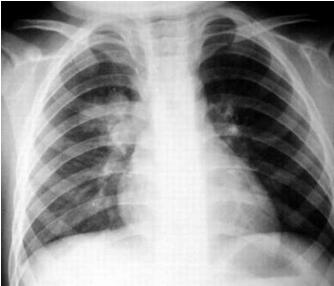

所谓支气管,字面上就可以理解,支气管炎是排行气道膜,或者,支气管的炎症,炎症影响到气管周围组织,在胸片上可以显示肺纹理增强模糊,这就叫支气管肺炎,影响范围是肺泡

而小儿肺炎,如果炎症影响到肺组织,胸片或胸透看见有大片的或斑片状阴影,就叫肺炎。这些得需要通过观察胸片才可以察觉

而小儿肺炎是由病原体感染或吸入羊水及油类和过敏反应等所引起的肺部炎症,通过X线胸片可直接反映患儿肺部病变情况,是诊断肺炎的重要依据,并且可通过X线所示,区别是何种类型肺炎。如支气管肺炎,多表现为非特异性小斑片状肺实质浸润阴影;大叶肺炎为大片阴影均匀而致密,占全肺叶或一个节段。